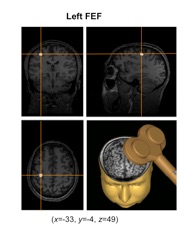

Chica et al.

Scientific Reports (2016)

Cerebral Cortex (2014)